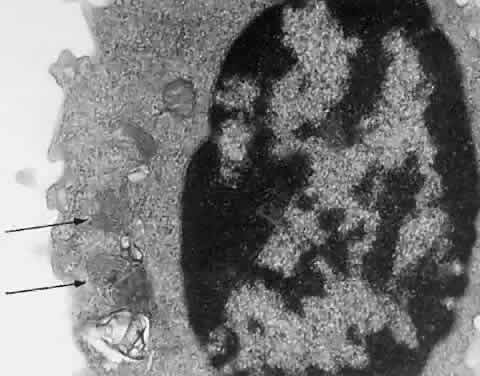

The pathologic hallmark of types A and B is the Niemann-Pick cell, which is a lipid-laden foam cell133 (Fig. 14). Sphingomyelin accumulates in the brain and autonomic ganglia. The neurons become swollen and have a pale cytoplasm. Ultrastructurally, the cells contain concentric lamellated bodies representing storage cytosomes. Inclusion profiles in the viscera, lymph nodes, and foam cells also correlate with an increase in sphingomyelin content. Diagnosis can be made readily by enzymatic determination of ASM activity in cells and tissues. More than 300 cases of type A and B NPD have been reported. Prenatal diagnosis has been accomplished by enzyme assays of cultured amniotic fluid cells in types A and B.

Fig. 14. Foam cells in bone marrow aspirate of patient with Niemann-Pick type B. Giemsa stain.